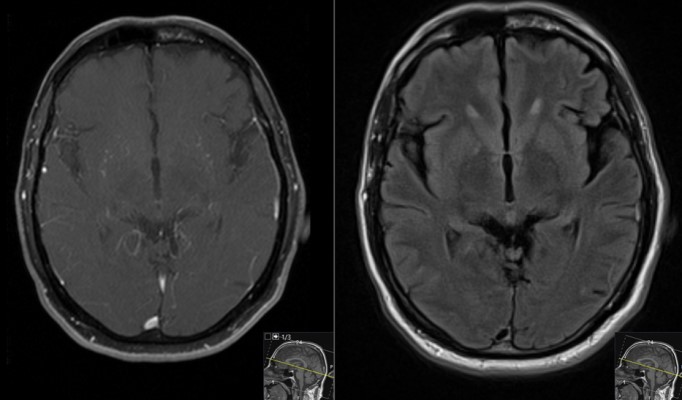

This is a 69 year old male with a known history of renal cell carcinoma who presented with cognitive decline and a neck mass.He had memory issues which were attributed to chemotherapy. He also was having new headaches. The neck mass was due to an infection. Neurologic examination was relatively unremarkable.

- Pre-Op